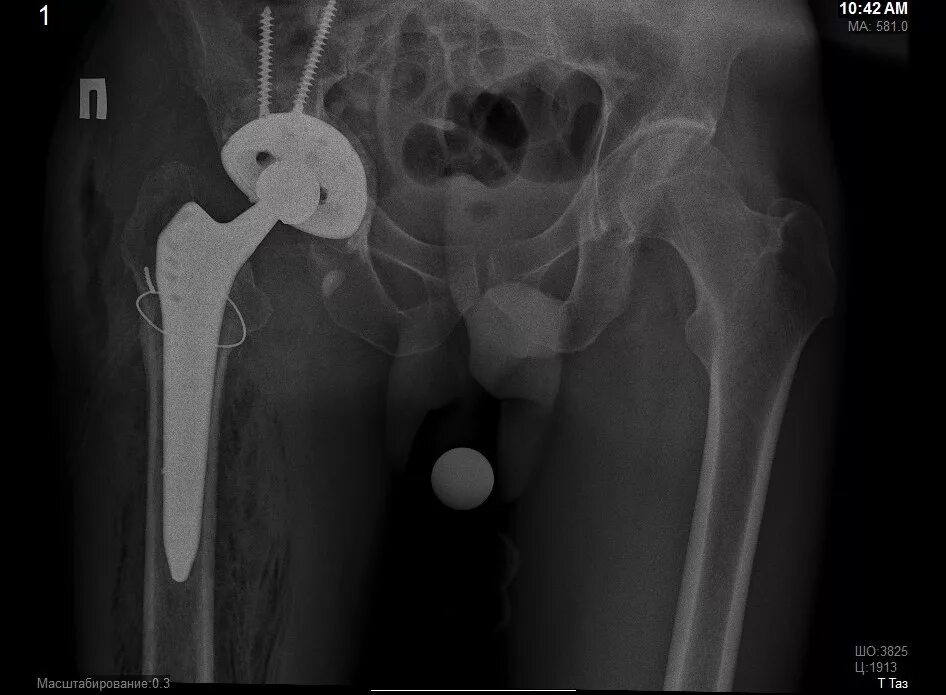

Ревизия тазобедренного сустава